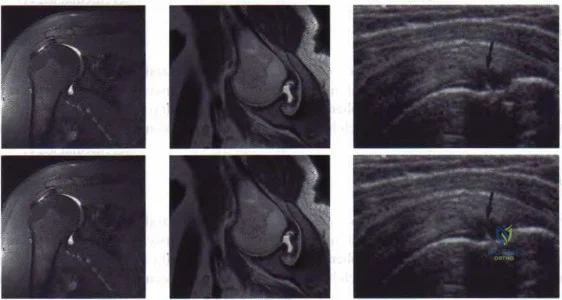

Review the intraoperative image.

During a revision total knee arthroplasty, restoring the native joint line is critical for optimal outcome. What is the most reliable bony landmark to determine the native joint line level?